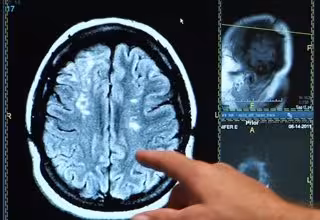

Un estudio evidencia diferencias asociadas al género en las hemorragias cerebrales

Ictus, derrame cerebral, cerebro

Neurólogos del Hospital del Mar de Barcelona e investigadores del Instituto Hospital del Mar de Investigaciones Médicas (IMIM) han evidenciado diferencias asociadas al género en las hemorragias cerebrales, al constatar que los hombres las sufren seis años antes y la localización del hematoma es más profundo que en las mujeres.

También se han observado diferencias en la localización del hematoma cerebral; en hombres es más frecuente el hematoma profundo, mientras que en mujeres es más común en la zona lobular del cerebro, más superficial.